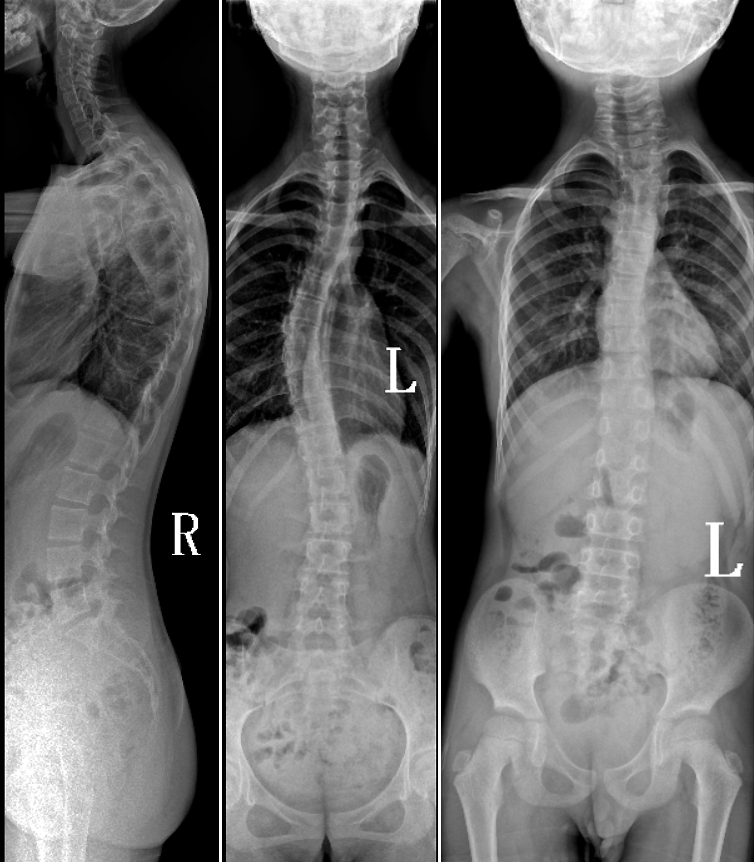

DR是臨床骨科的重要檢查手段之一。在骨科檢查中,脊柱矯形、長骨骨折、腰椎退行性病變等,需要采集脊柱、下肢全景圖像,輔助醫(yī)生臨床診斷,從而制定科學的治療方案,普愛醫(yī)療的大視野平板動態(tài)DR就像是一座橋梁,連接起現(xiàn)代醫(yī)療技術(shù)與當?shù)厝嗣竦尼t(yī)療需求。

普愛醫(yī)療自主研發(fā)的大視野平板動態(tài),采用17"*34"的有效視野,一次曝光即可得到全脊柱或全下肢影像。相較于多張攝影再軟件拼接的DR設備,PLX8600解決了拼接圖像存在密度不均勻,拼接處圖像配準和放大效應等問題,給臨床帶來了真正的大視野影像解決方案。